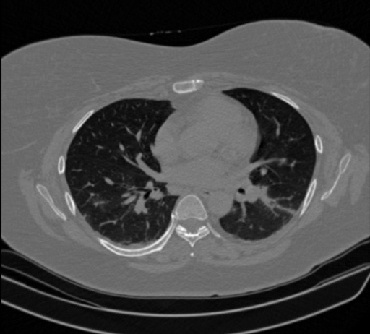

It should be mentioned that for explainability purposes [7, 8, 9], an anchor set was generated for the COV19-CT-DB database [5]. This included 11 anchors, each representing a respective 3-D CT scan obtained through an appropriate clustering procedure. Figure 2 shows a series of slices from a COVID-19 case, whereas Figure 3 shows a series of slices from a non COVID-19 case.